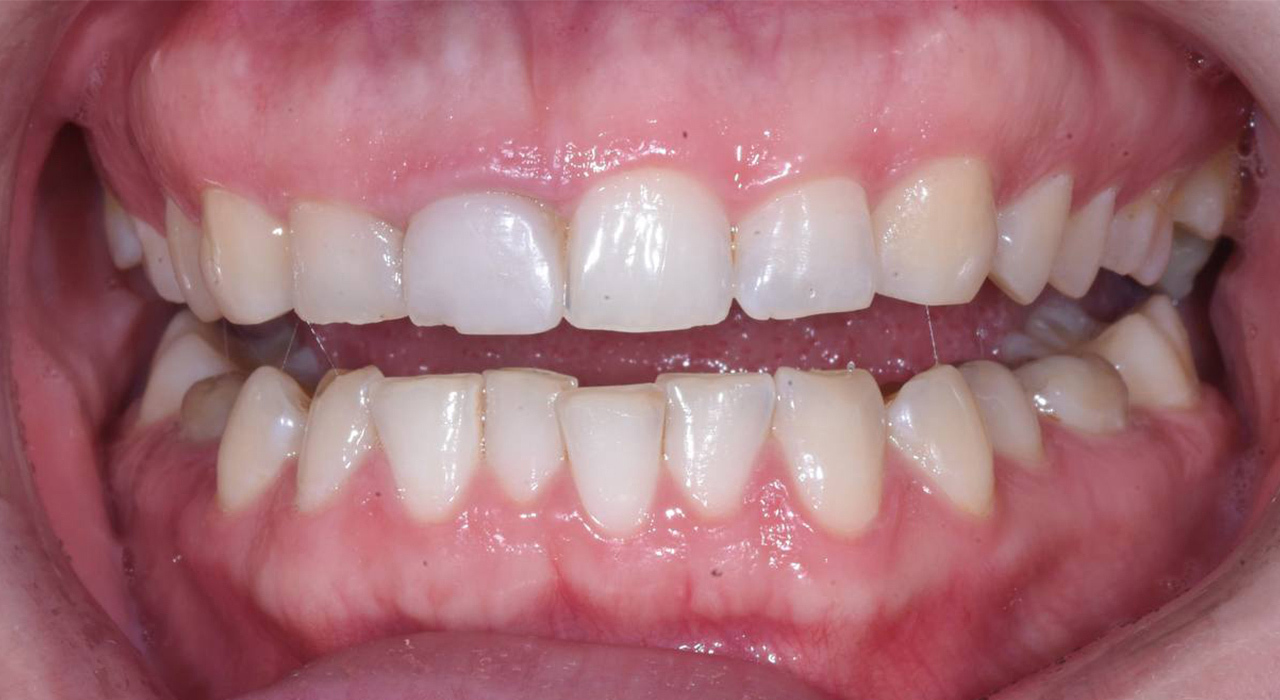

Подготовка к постоянному протезированию – примерка прототипов будущих зубов после остеоинтеграции имплантов